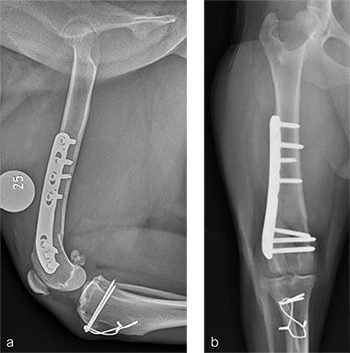

A routine lateral approach to the distal femur and stifle joint was performed. Results of the cruciate ligaments examination were normal. The lateral joint capsule was dissected to expose the distal femoral condyle. An alignment jig was placed in a craniocaudal direction to ensure that deformity correction was limited to the frontal plane. A 12 lateral closing wedge ostectomy was performed and the femoral condyle was reduced and temporarily stabilized with divergent K-wires. A 7-hole left 3.5 LCP DFO plate was placed on the lateral femur and secured with a combination of 3.5 mm cortex and locking screws. The compression function of the plate was used to compress the ends of the two bone segments. Temporary K-wires were removed and a wedge sulcoplasty was performed to deepen the trochlear groove for improved patella articulation. A tibial tuberosity transposition was performed and stabilized with two pins and tension band wire. Routine closure was performed. Total surgical time was 1 hour and 45 minutes. Postoperative x-rays demonstrate the position of a left, 7-hole, 3.5 LCP DFO plate and associated tibial tuberosity transposition. In the medioateral view it can be appreciated that plate contour matches the normal distal femoral procurvatum and screws are positioned caudally away from the trochlea (Fig 6a). This allows for an unimpeded sulcoplasty while maximizing screw purchase caudally. The compression applied with the plate has resulted in excellent apposition. The patella is visible within the trochlear groove. In the craniocaudal view the plate contour matches the anatomical contour of the distal femoral condyle (Fig 6b). The anatomical Lateral Distal Femoral Angle is reduced to 92. During the follow up after 8 weeks, clinical signs have resolved, limb use is excellent, and stifle joint range of motion is normal without evidence of pain. In the mediolateral x-ray the osteotomy has healed (Fig 7a). Plate and screw position remain unchanged. The tibial tuberosity transposition is healing, and implants remain unchanged. The patella remains reduced within the trochlear groove. In the craniocaudal view the osteotomy has healed and is no longer visible (Fig 7b). Implants are stable and the patella is tracking normally.